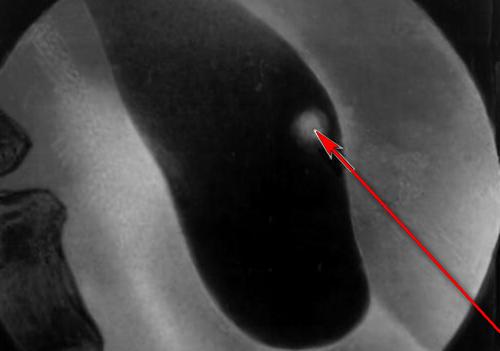

Многих интересует вопрос – лечит ли полынь полипы? Желчный пузырь при застоях желчи подвержен формированию не только этих новообразований, но и камней, и полынь горькая является эффективным народным средством как при полипозе, так и при камнях в желчном пузыре. Кроме того, её назначают и при других патологиях этого органа, а также при болезнях почек и при воспалениях прямой кишки.